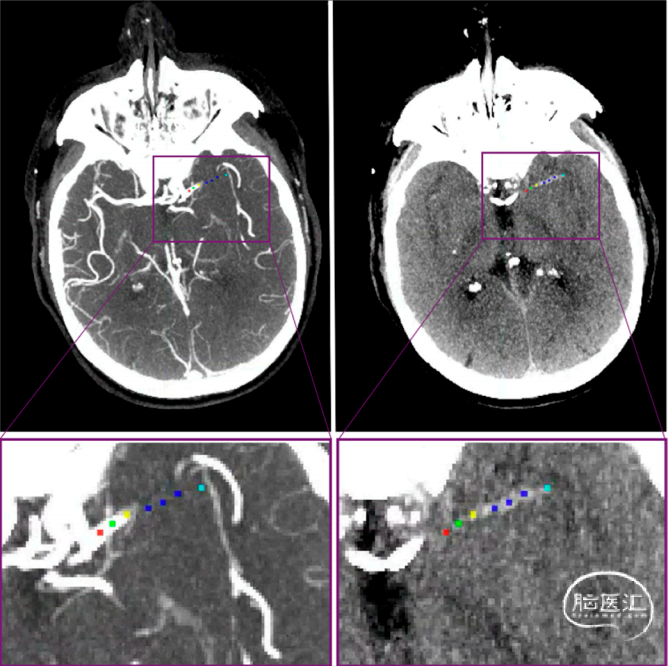

图1. 血栓的影像学特征。

人工放置标记物计算血栓特征。左图:CT血管造影的厚板最大密度投影,显示由于闭塞导致造影剂突然停止。右图:非对比CT厚板最大强度投影,可见血栓高密度征象。红色标记:位于颈内动脉末端(ICA-T)。绿色标记:位于ICA-T与血栓近端边界之间。黄色标记:近端血栓边界。蓝色标记:血栓的近端、中端和远端。青色标记:血栓远端边界。